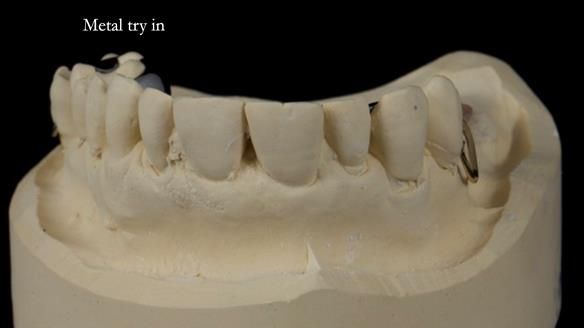

Welcome to Newsletter 64. I'll walk you through the process of providing a Mk 2 metal-based partial denture (RPD), for Ian a retired Veterinary Surgeon aged 78. The RPD was made at an increased vertical dimension and acted as an occlusal stabilisation splint - reducing the wear and bite force on the remaining natural teeth.